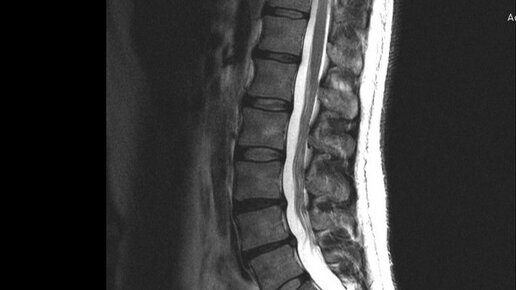

МРТ пояснично-крестцового отдела (она же МРТ поясничного отдела позвоночника) является приоритетным способом диагностики патологий области поясницы. В большинстве случаев направление на томографию позвоночника выдает невролог или хирург...